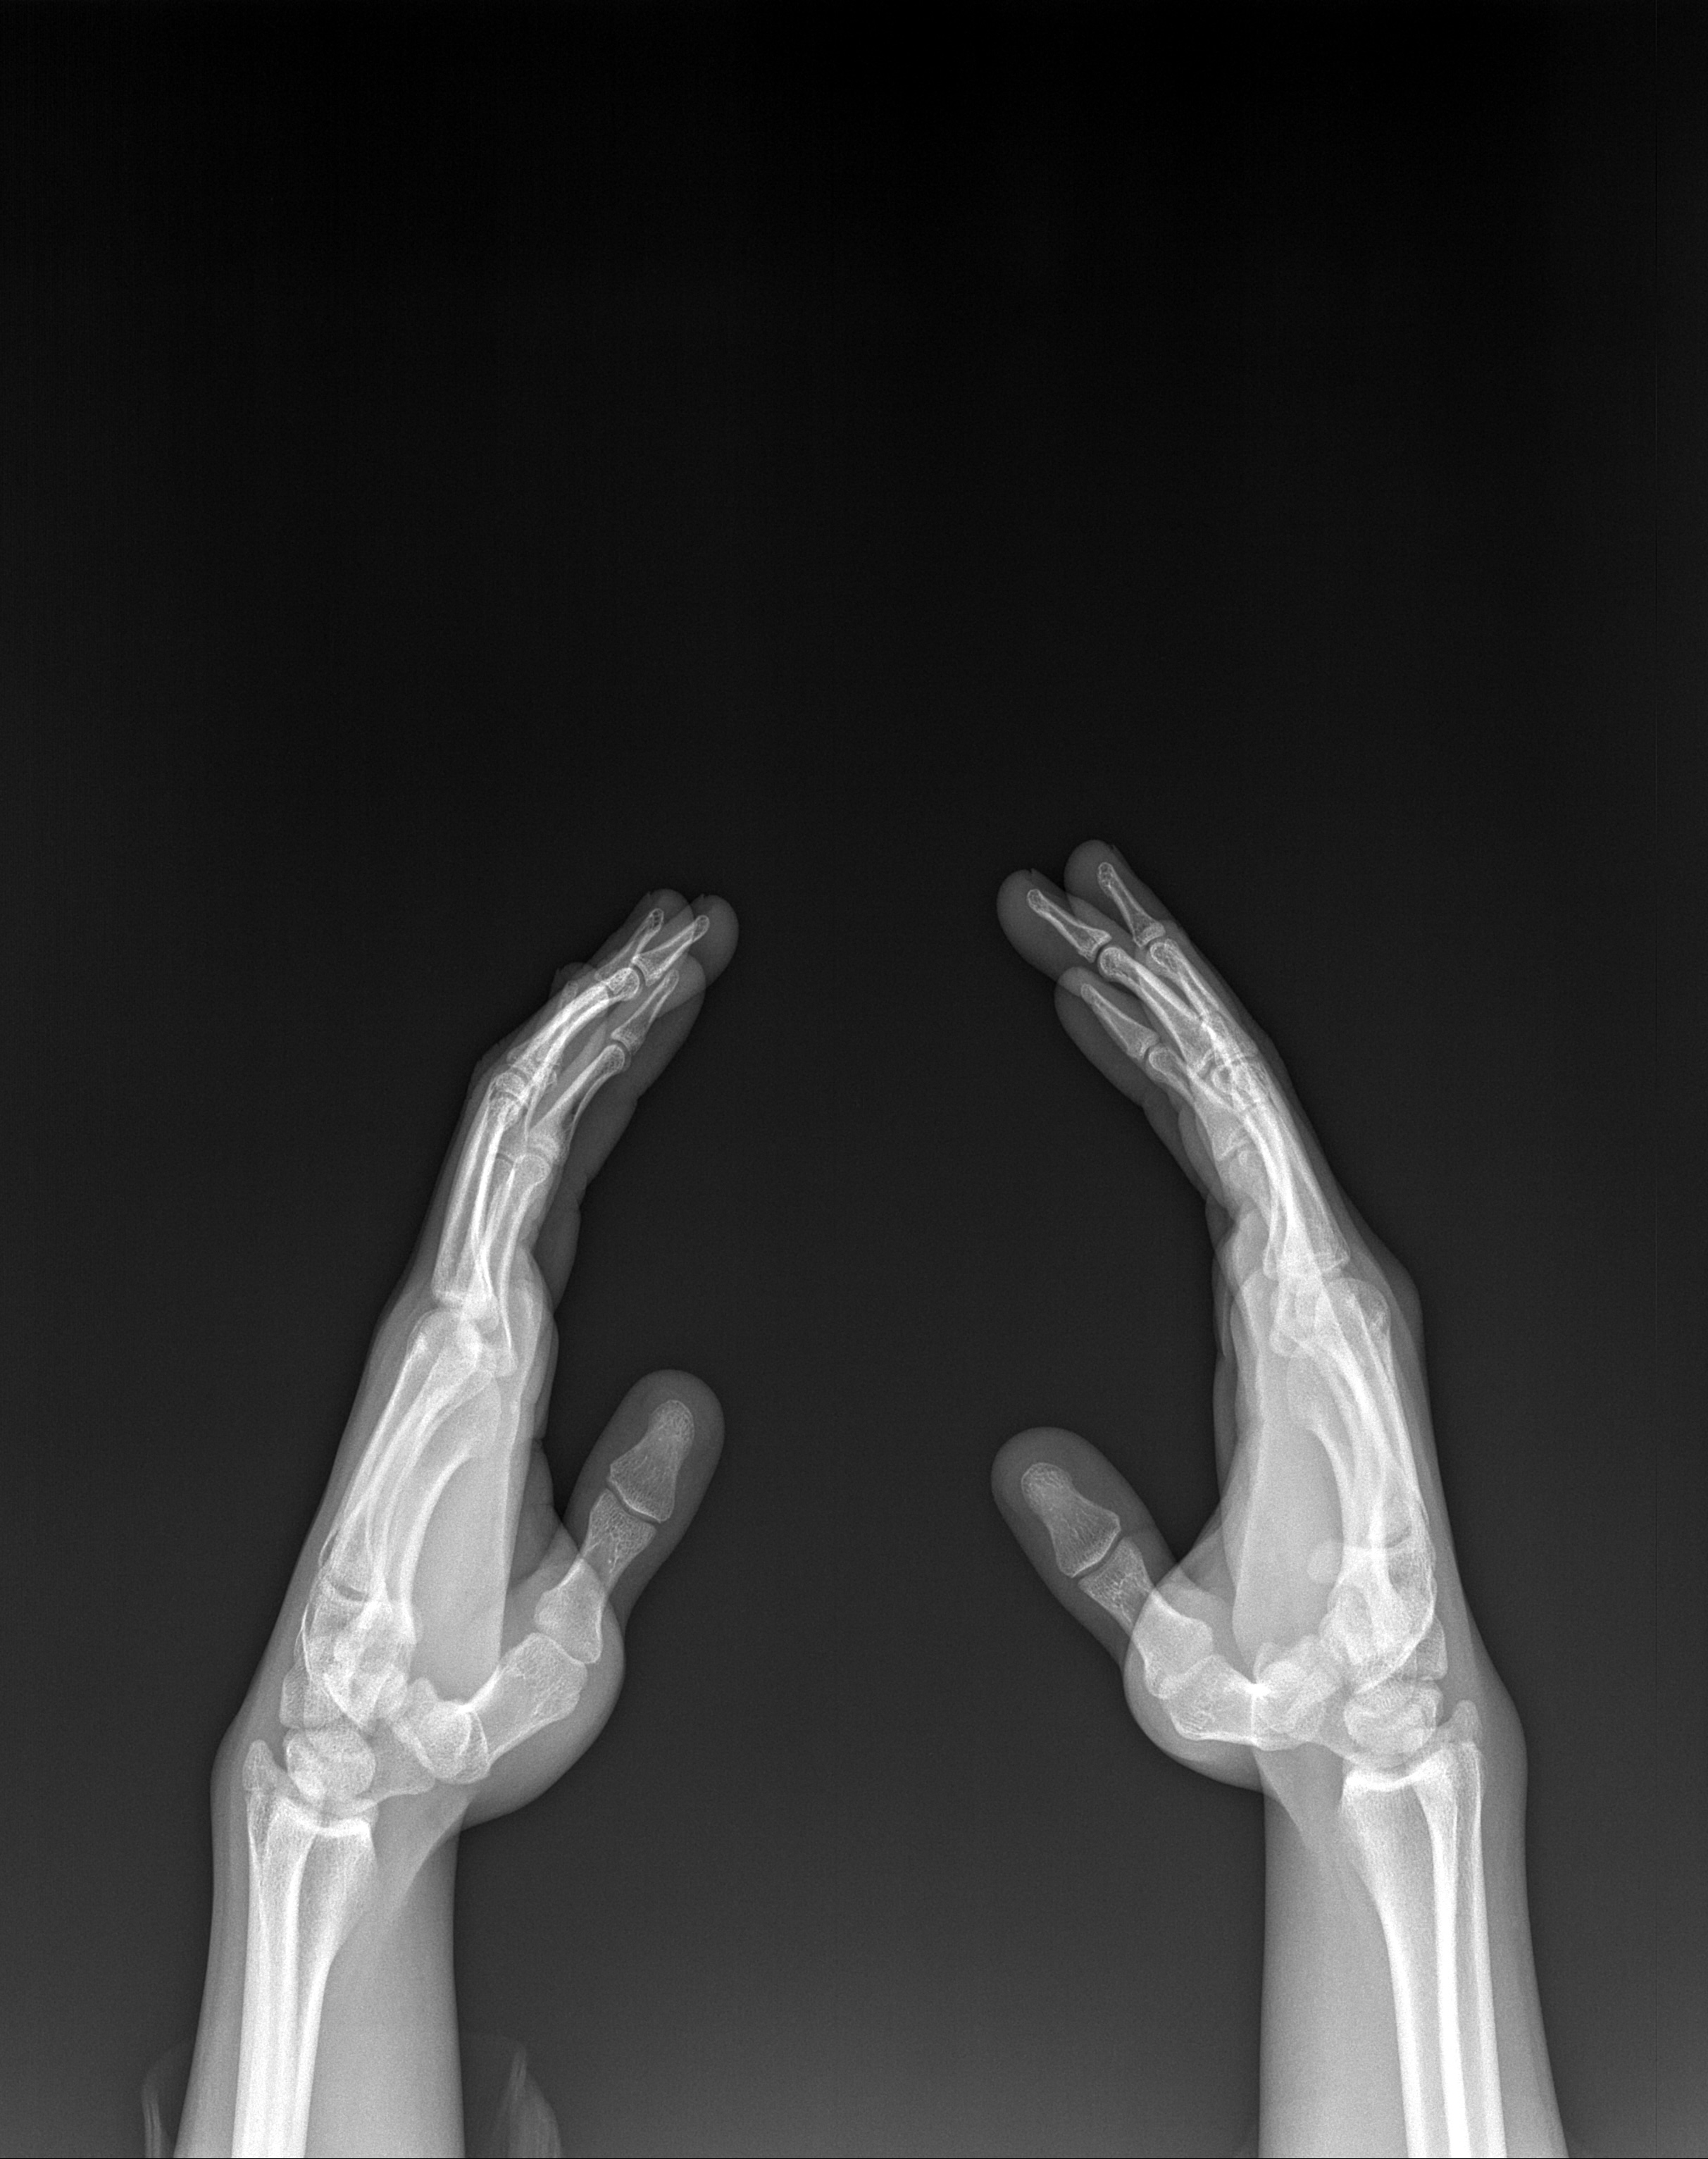

Ne diyonuz açık kapalı

parmaktakiler kapalı ama düzgün röntgen yok mu böyle emin değilim

Açıkla Karşılaştırma yaptımda kapalı diye yorumladım dize baktırcam artık bidahaki röntgende